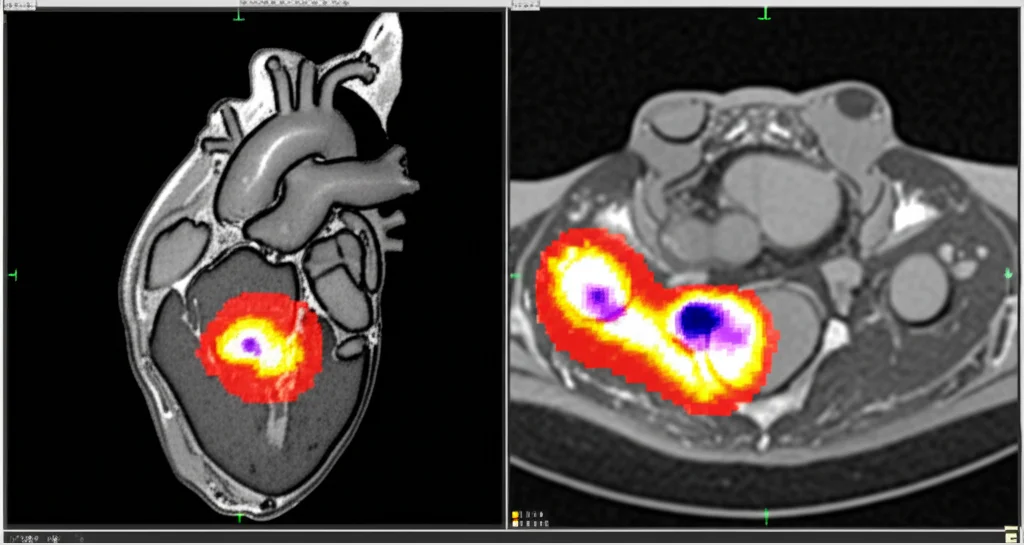

Quando analizziamo queste immagini, non cerchiamo solo l’infarto (MI) in sé. Dobbiamo identificare diverse regioni chiave: la cavità ventricolare sinistra (LV), il miocardio sano (Myo), l’area infartuata (MI) e, a volte, una complicanza chiamata ostruzione microvascolare persistente (MVO). Quest’ultima è particolarmente insidiosa perché è associata a una prognosi peggiore e a un maggior rischio di eventi avversi.

La segmentazione si occupa di tracciare i confini delle quattro regioni chiave (LV, Myo, MI, MVO). Per farlo, abbiamo usato un modello di deep learning chiamato ResU-Net, una variante potenziata del famoso U-Net, che si è dimostrato molto efficace.

- Segmentazione: Il nostro ResU-Net ha ottenuto punteggi F1-score elevati: 91.12% per LV, 88.39% per Myo, 80.08% per MI e 68.01% per MVO. È riuscito a delineare bene anche le aree più piccole e difficili.

Un aspetto cruciale quando si parla di IA in medicina è la fiducia. I medici devono poter capire *perché* un algoritmo prende una certa decisione. Per questo, abbiamo integrato tecniche di Explainable AI (XAI), come le mappe di calore Grad-CAM. Queste mappe evidenziano visivamente quali parti dell’immagine MRI sono state più influenti per la decisione del modello. È come poter sbirciare “nella mente” dell’IA e vedere su cosa si è concentrata per fare la diagnosi. Questo non solo aumenta la fiducia, ma aiuta anche a identificare potenziali errori o bias.